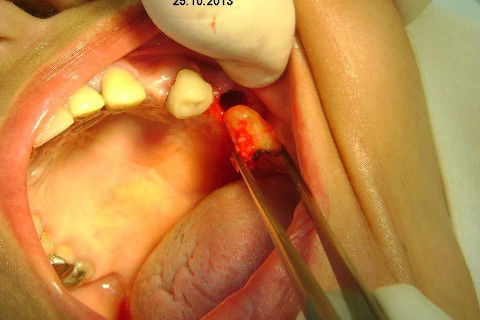

Ao exame clínico já percebemos atrofia no rebordo, uma depressão na vestibular, indicação para enxerto ósseo e dente 27 com indicação para remoção. O plano de tratamento consistiu em levantamento de seio maxilar deste lado para possibilitar instalação de implante na região do 26 (não existe dente antagônico para oclusão com o 27), enxerto ósseo na vestibular do dente 24, aproveitamento do 22,23,25, em situação satisfatória, com indicação de confecção de novas coroas.

A minha intenção era levantamento de seio e enxerto na vestibular do 24 em única sessão, mas a pedido da paciente, resolveremos o caso por etapas, consideramos a prioridade da resolução desta região dos pré molares e fizemos esta cirurgia de hoje, usando osso autógeno coletado da região da tuberosidade e próximo do alvéolo do 27. Usamos também osso bovino liofilizado Bonefill (Bionnovation) granulação média, e tela de titânio Surgitime (Bionnovation). Não foi possível a instalação do implante em conjunto com o enxerto por considerarmos rebordo extremamente atrófico na espessura (menos de 2 mm na crista e menos de 3 mm até acima do terço médio).